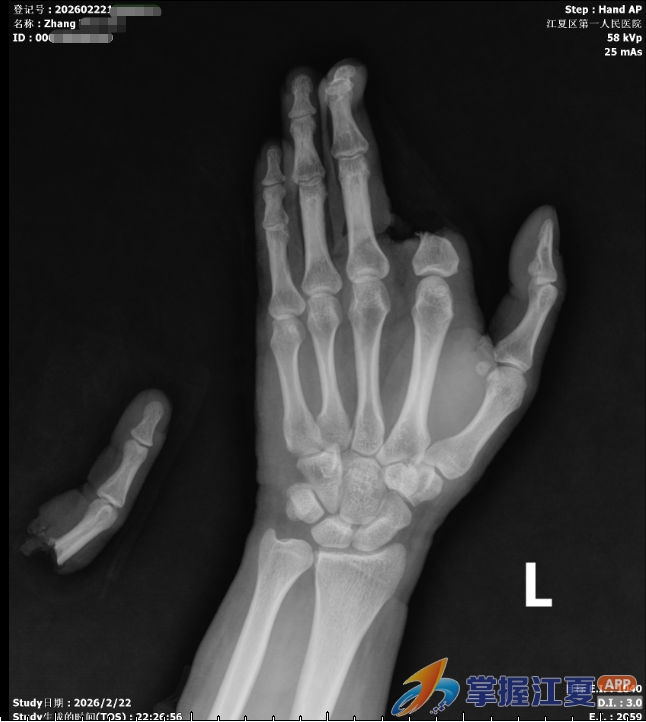

这场“生命竞速”始于2月22日(农历大年初六)晚。当晚10时35分,张先生被朋友紧急送入江夏区第一人民医院(协和江南医院)急诊科。医生发现其左手被电锯严重割伤,导致其左手食指自掌指关节处完全离断,仅少许皮肤相连;左手中环小指掌指关节处可见一约6cm横行伤口,活动性出血,创面软组织挫伤严重。“我当时脑子一片空白,就看见血不停地涌出来,心想‘这只手怕是要废了’。”据张先生回忆。

“对于完全离断的指体,缺血时间越短,再植成活率越高。我们必须争分夺秒,启动绿色通道,为再植争取最大的‘黄金窗口期’。”该院手外科主任陈冬生副主任医师表示,食指(示指)是进行精细操作和力量性抓握的关键,保住它,就是保住患者未来的手部功能与劳动能力。“在无明显手术禁忌证下,连夜协调手术室,拟定在神经丛阻滞麻醉下行‘左手示指再植及左手伤口清创缝合+神经肌腱血管探查修复术’。”